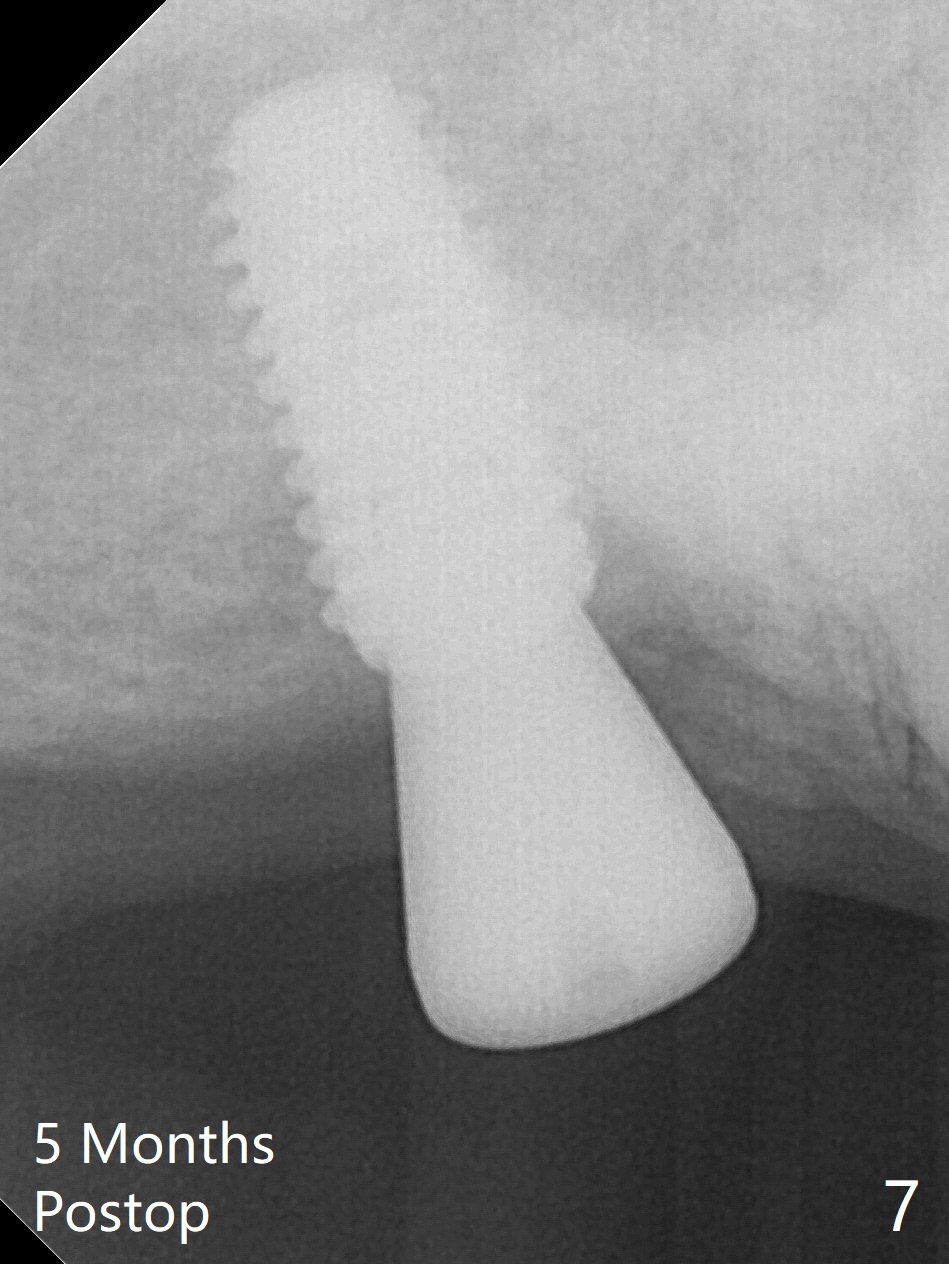

Two things happen immediately before this surgery. A SM implant is found to fail related to bruxism and poor oral hygiene, ~ 5 years in function; a UF implant will be used instead. DIO Sinus Approach Kit has not been autoclaved; therefore the free-hand one has to be used with caution. In fact the procedure goes on apparently smoothly in spite of the fact that the patient with medical knowledge is nervous about the risk of sinus lift. After 4.0x8.5 mm Neo Navi drill with 12 mm offset, the 3.6 mm sinus safety drill is used from 7 to 9 mm in length, followed by water balloon, PRF membranes (x2) and mixture of autogenous bone graft and allograft and 4.5x10 mm dummy implant (Fig.1). The definitive implant is placed with satisfactory stability (Fig.2), but a 6.5x7(4) mm healing abutment is close to the mesial crest (*). The former is reloaded following 6.0 mm Bone Profile Drill (Fig.3) and then is changed to a 6x6 mm IS one. The patient reports nasal hemorrhage immediately returning home, but there is no similar episode a few hours later. Re-analysis of preop (Fig.4) and immediate postop (Fig.5) CT shows that water balloon technique in fact swells the sinus membrane (M) instead elevating it. It is safe to place more bone graft (Fig.5 *). There is pain when the 6x6 mm healing abutment is being removed nearly 5 months postop (Fig.6.7). The patient complains of mild sinus discomfort, although panoramic X-ray does not show abnormality (Fig.8). He will return for recheck for implant stability (low bone density) before impression 2-4 months later.